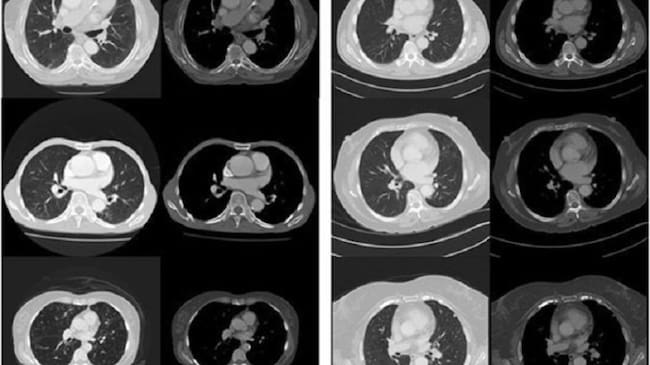

Distintos tipos en el análisis de la arteria coronaria. / Cadena SER

Un estudio de la Universidad de Adelaida, en Australia, desvela el método por el que los pacientes podrán saber cuánto tiempo les queda de vida. A través de la inteligencia artificial (IA), los órganos son fotografiados para analizar su interior.

La prueba ha sido realizada a través de 48 pacientes. Las imágenes obtenidas de sus órganos fueron analizadas a través de tres filtros establecidos en el estudio y esto fue capaz de predecir cuántos pacientes tenían una esperanza de vida de menos de cinco años con un precisión del 69%.